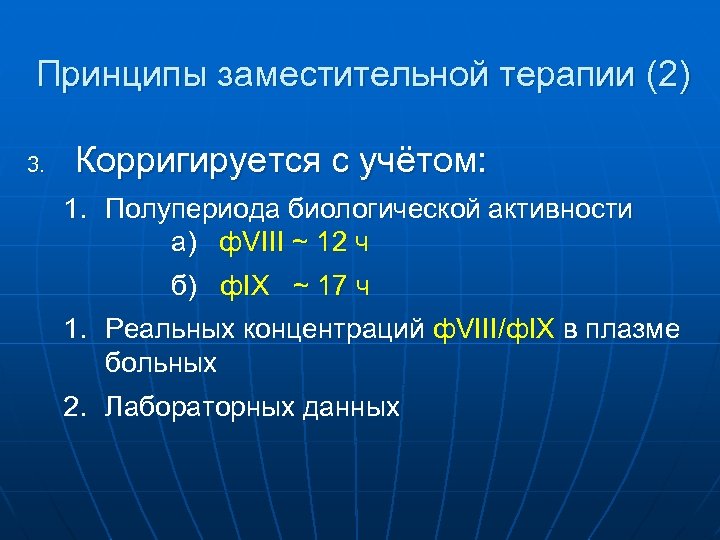

Принципы заместительной терапии (2) 3. Корригируется с учётом: 1. Полупериода биологической активности а) ф. VIII ~ 12 ч б) ф. IX ~ 17 ч 1. Реальных концентраций ф. VIII/ф. IX в плазме больных 2. Лабораторных данных